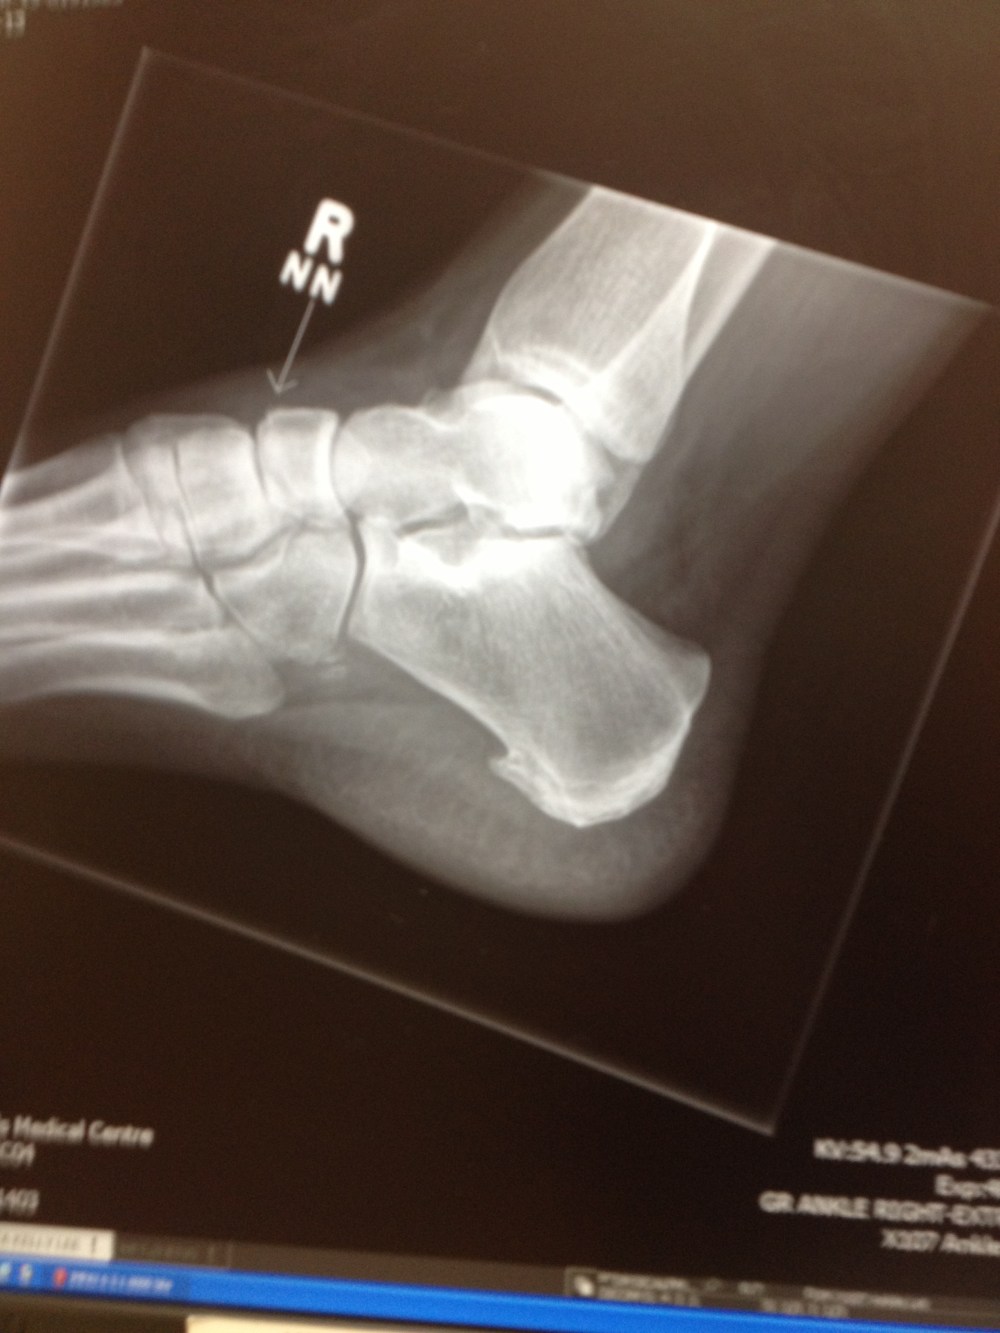

Broken Ankle

IMG_0218A few weeks ago, I was out walking my dog with a friend.  We had gone fewer than 30 yards when I turned my ankle in a small divot in the ice and fell down, breaking my fibula and tibia in the process.  The break required surgery and the placement of a total of one plate and eight screws in my bones.  As I lay in the hospital waiting to be mended, I thought about the advancement of technology and how it has transformed my life, for the better and for the worse.